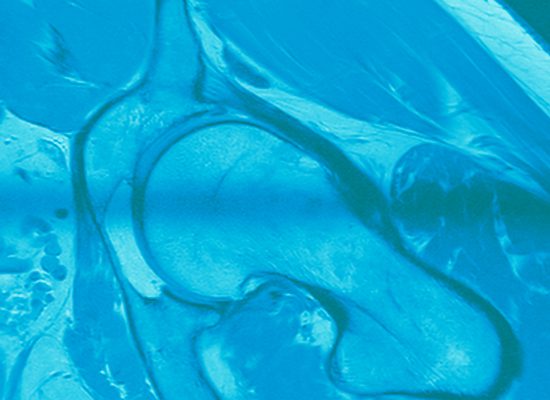

002 Hüften radial